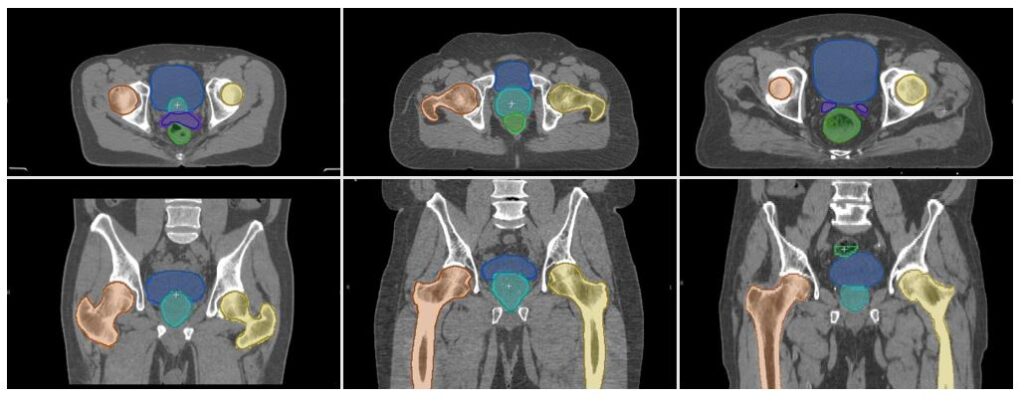

Radiotherapy planning workflow using CT images

An important potential application for machine learning in medical imaging is to assist clinicians for image preparation and planning tasks in radiotherapy cancer treatment workflows (opens in new tab). Our latest research, published in JAMA Network Open, shows how AI can augment and accelerate clinicians’ ability to perform radiotherapy planning 13 times faster. For details of how you can make use of the InnerEye OSS tools for radiotherapy planning workflows with CT images see our Getting started section. Support is via GitHub Issues on the relevant repositories only.

Radiology and surgery planning with CT images

The InnerEye-DeepLearning Toolkit (opens in new tab) makes it easy to use pre-configured neural networks, such as UNet3D, or bring-your-own-models (opens in new tab) for CT images. Potential use cases for this are quantitative radiology and surgery planning. Use of the Gateway and Inference Services will require additional software engineering effort by you. Support for these use cases is via GitHub Issues on the relevant repositories only.